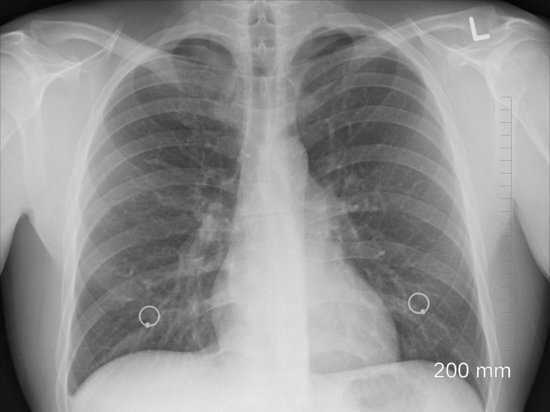

Ольга, вы видимо сами не до конца всё поняли. Не в учебнике, а в журнале ЗОЖ (9 номер за 2003 г.). Сами найдите в интернете и прочитайте. Смотрела я на эту 3D модель. Да, очень красочно показано. А потом смотрела снимок лёгких. Или его специально так показали, чтобы несведующие люди ничего понять не могли или... Много я видела снимков лёгких и при пневмонии, и при туберкулёзе. А на этом снимке... извините. 2 кружочка, за которыми вы и под лупой ничего не увидите.

ЭТО КАРТИНКА почти здоровых лёгких,. РОЛИК СМОТРИТЕ.